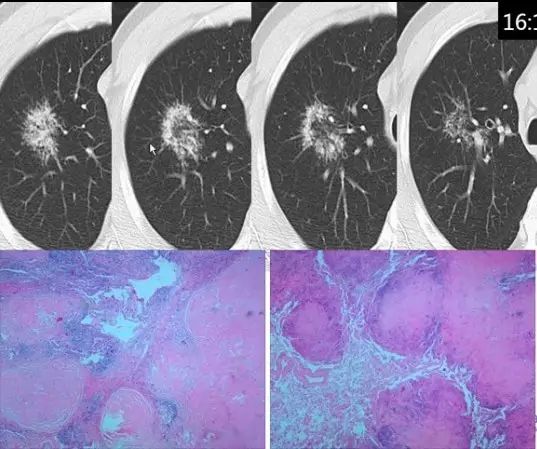

肺内“烟花征”,为活动性肺结核的CT表现之一。是结核经支气管播散并由多发小叶中央结节堆积而成,形态特征似烟花在空中散开。病理基础为细支气管及肺泡内干酪坏死性肉芽肿。